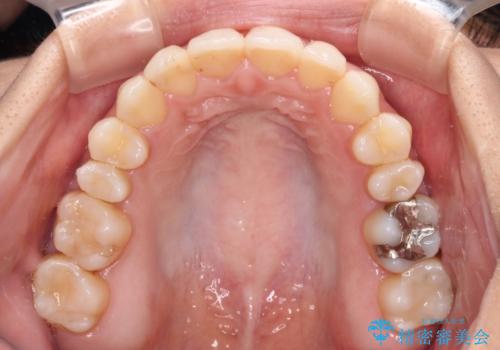

- オープンバイトのため、話しているときの見た目が気になるとのことで来院された患者様です。

下顎骨は左側にシフトしており、咬み合ったときには奥歯と前歯の一部しか接触していない状態でした。

骨格的な左右差は歯列矯正は改善できないため、上下歯列が全体的に接触することをゴールとしてインビザラインにて矯正治療を行うこととしました。

前歯のデコボコの解消と並行して上下の奥歯を圧下させるようにすることで、前歯を接触させるように計画しました。